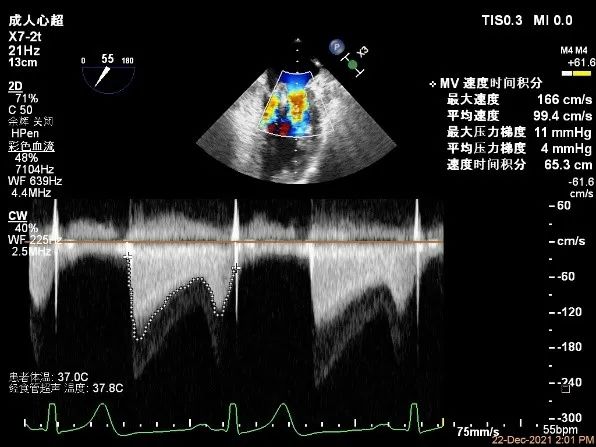

二尖瓣口平均跨瓣压差:4mmHg

第一个夹子放置侯二尖瓣口平均跨瓣压差:4mmHg

第二个夹子放置侯二尖瓣口平均跨瓣压差:4mmHg

3.由于脱垂范围较大,第一个夹子放置后被残余脱垂掀动,活动度较大,第二个夹子置入时减少呼吸潮气量,与第一个夹子尽量平行靠紧,应用TEE 3D调整优化夹子方向和位置,同时在DSA上确认,让第二个夹子“点头下降“”,与第一夹子靠近同轴“比翼双飞”,尽可能多的抓捕后叶,夹闭后第一个夹子活动度好转,MR残余分流立刻减少到微量,确认MV跨瓣压差5mmHg, 效果满意。